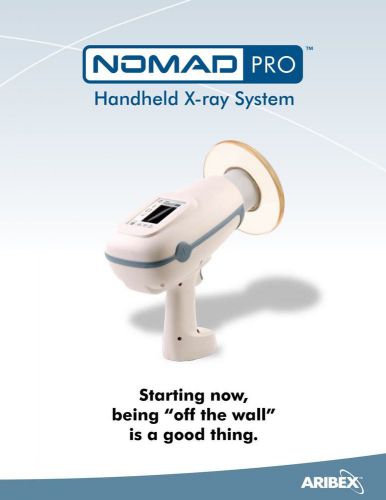

NOMAD Pro2 Handheld Portable Dental X-Ray by Aribex FREE SHIPPING